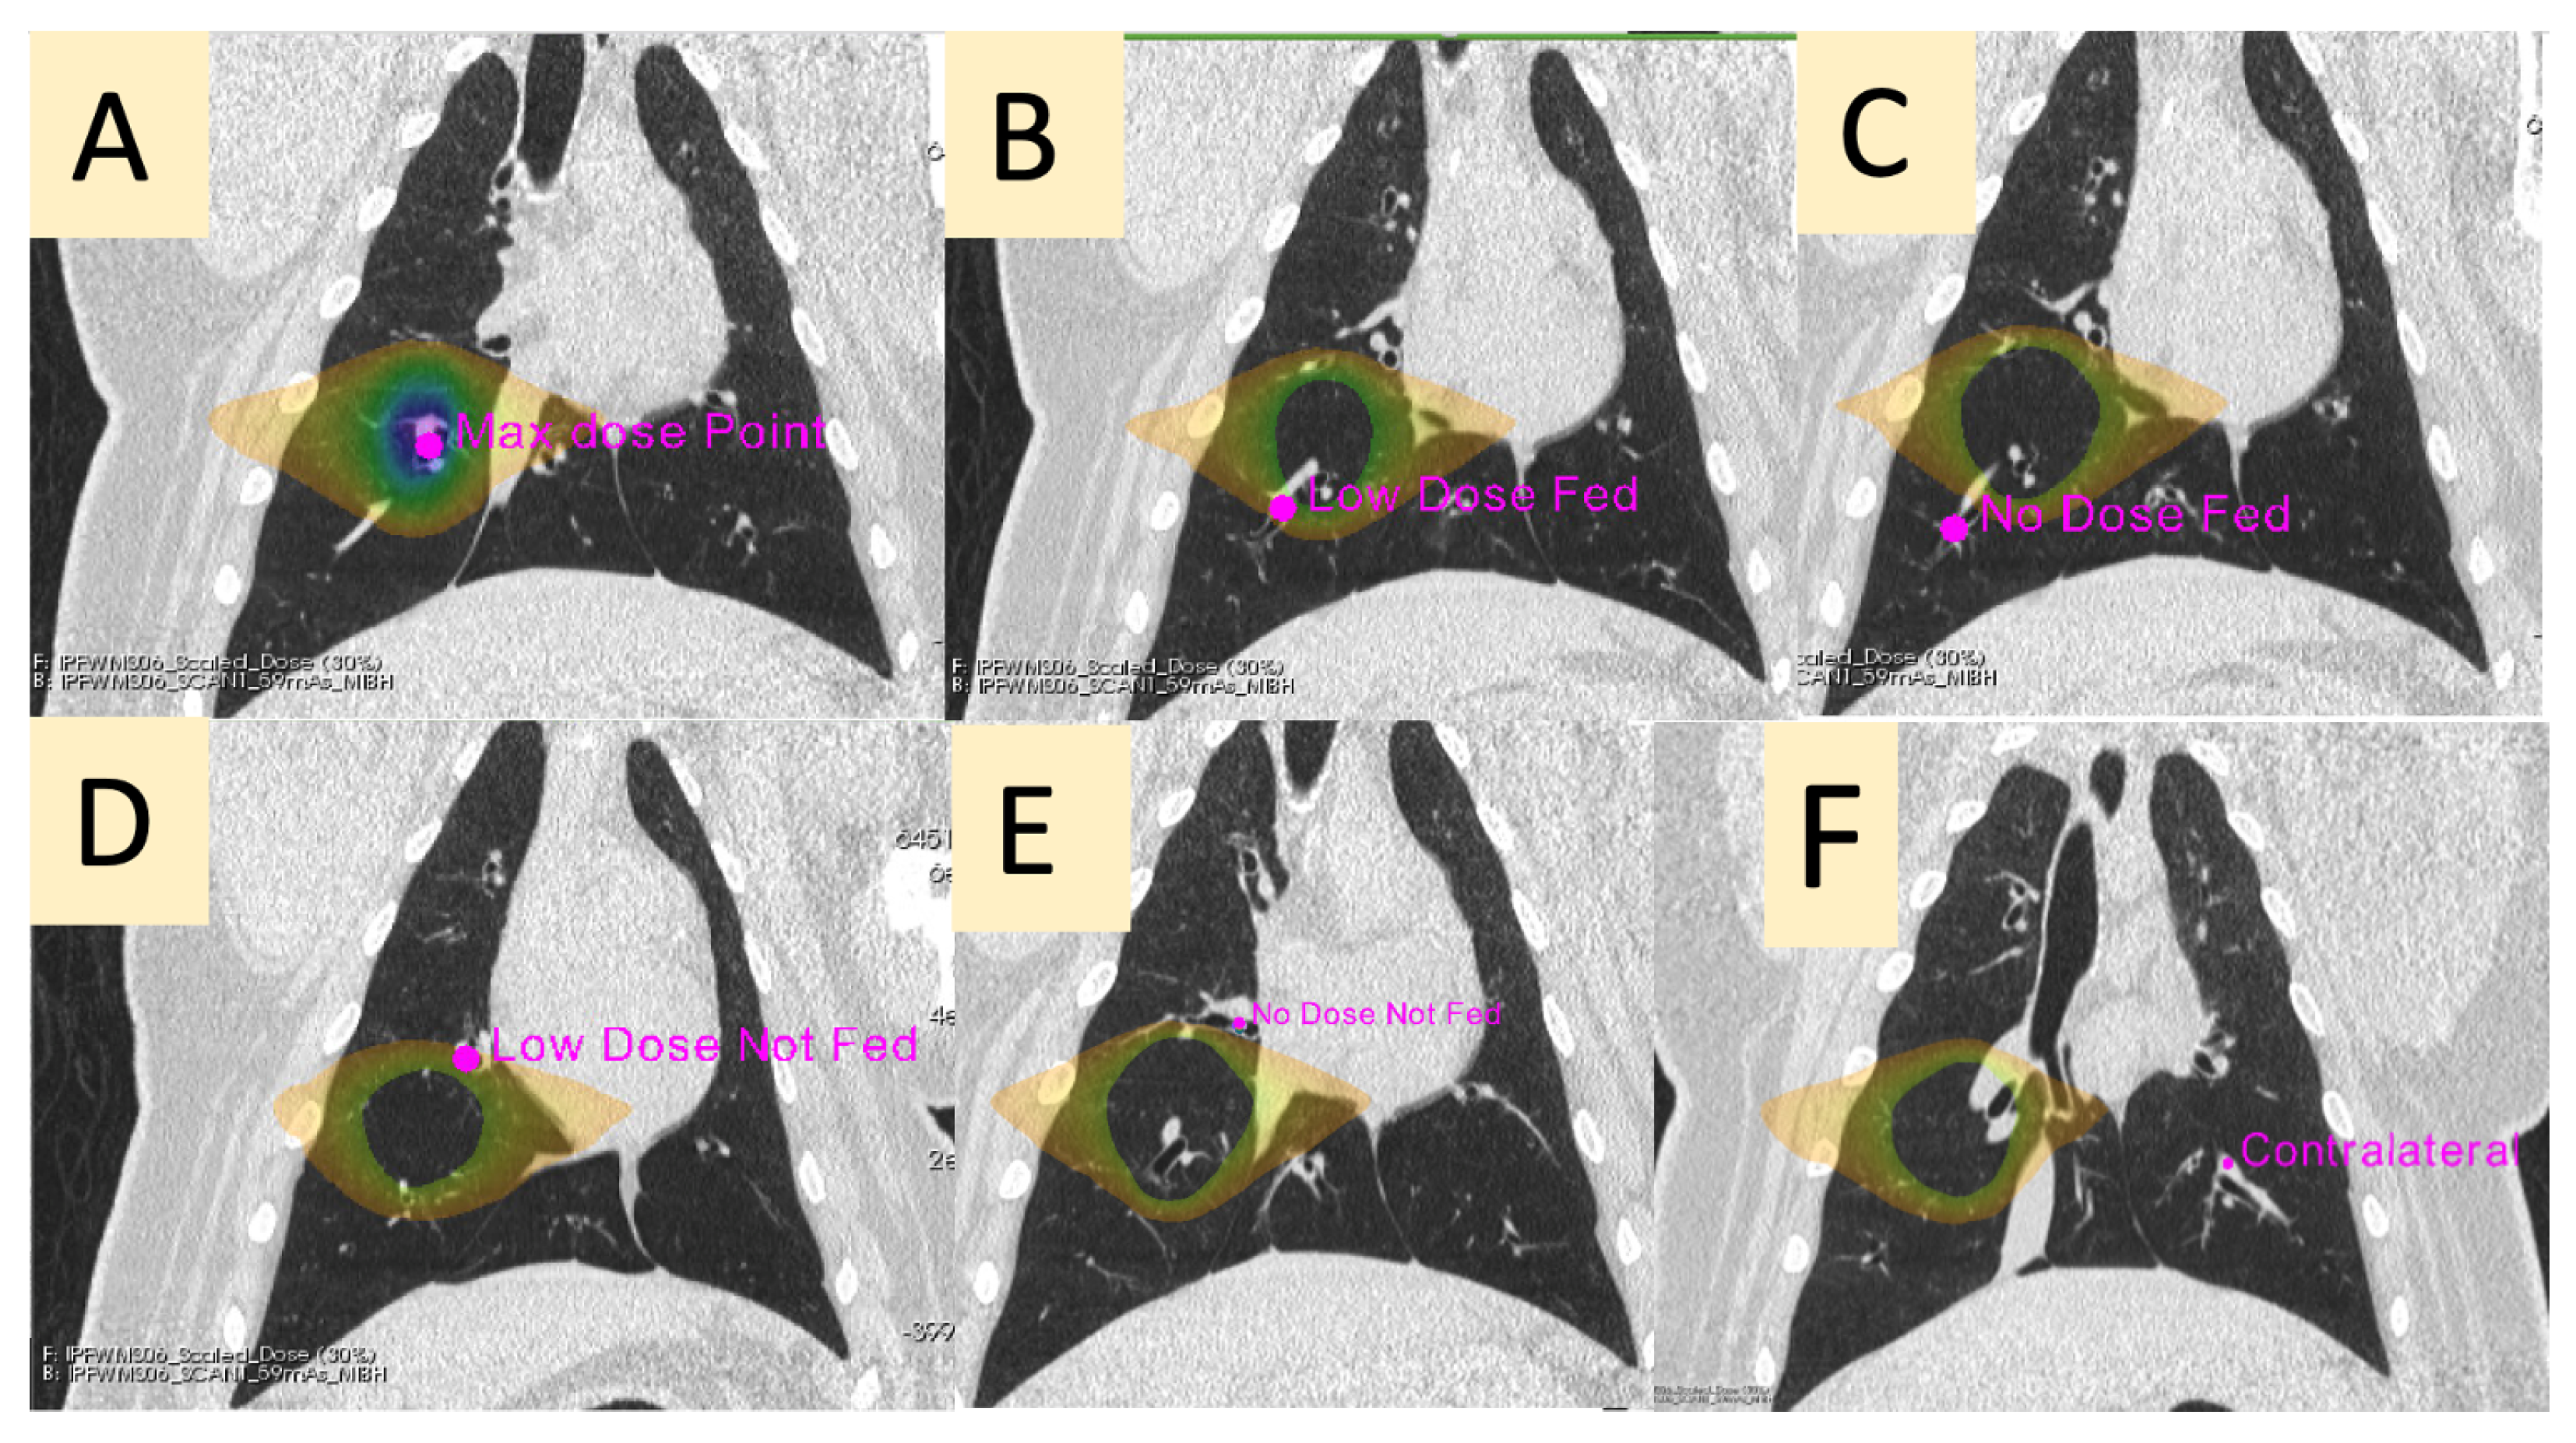

2.5. Regional Perfusion Analysis

| Contour Name | Description |

|---|---|

| Max Dose (MD) | The vessel contained in the PTV |

| Low-Dose Fed (LDF) | A vessel in the ipsilateral lung receiving between 5 and 20 Gy that branches downstream of the vessel irradiated to the max dose |

| No-Dose Fed (NDF) | A vessel in the ipsilateral lung receiving less than 5 Gy that branches downstream of the vessel irradiated to the max dose |

| Low-Dose Not-Fed (LDNF) | A vessel in the ipsilateral lung receiving between 5 and 20 Gy that does not branch from the vessel irradiated to the max dose |

| No-Dose Not-Fed (NDNF) | A vessel in the ipsilateral lung receiving less than 5 Gy that does not branch from the vessel irradiated to the max dose |

| Contralateral (CON) | A vessel in the contralateral lung (received no dose) at the approximate mirrored location as the point of max dose in the ipsilateral lung |